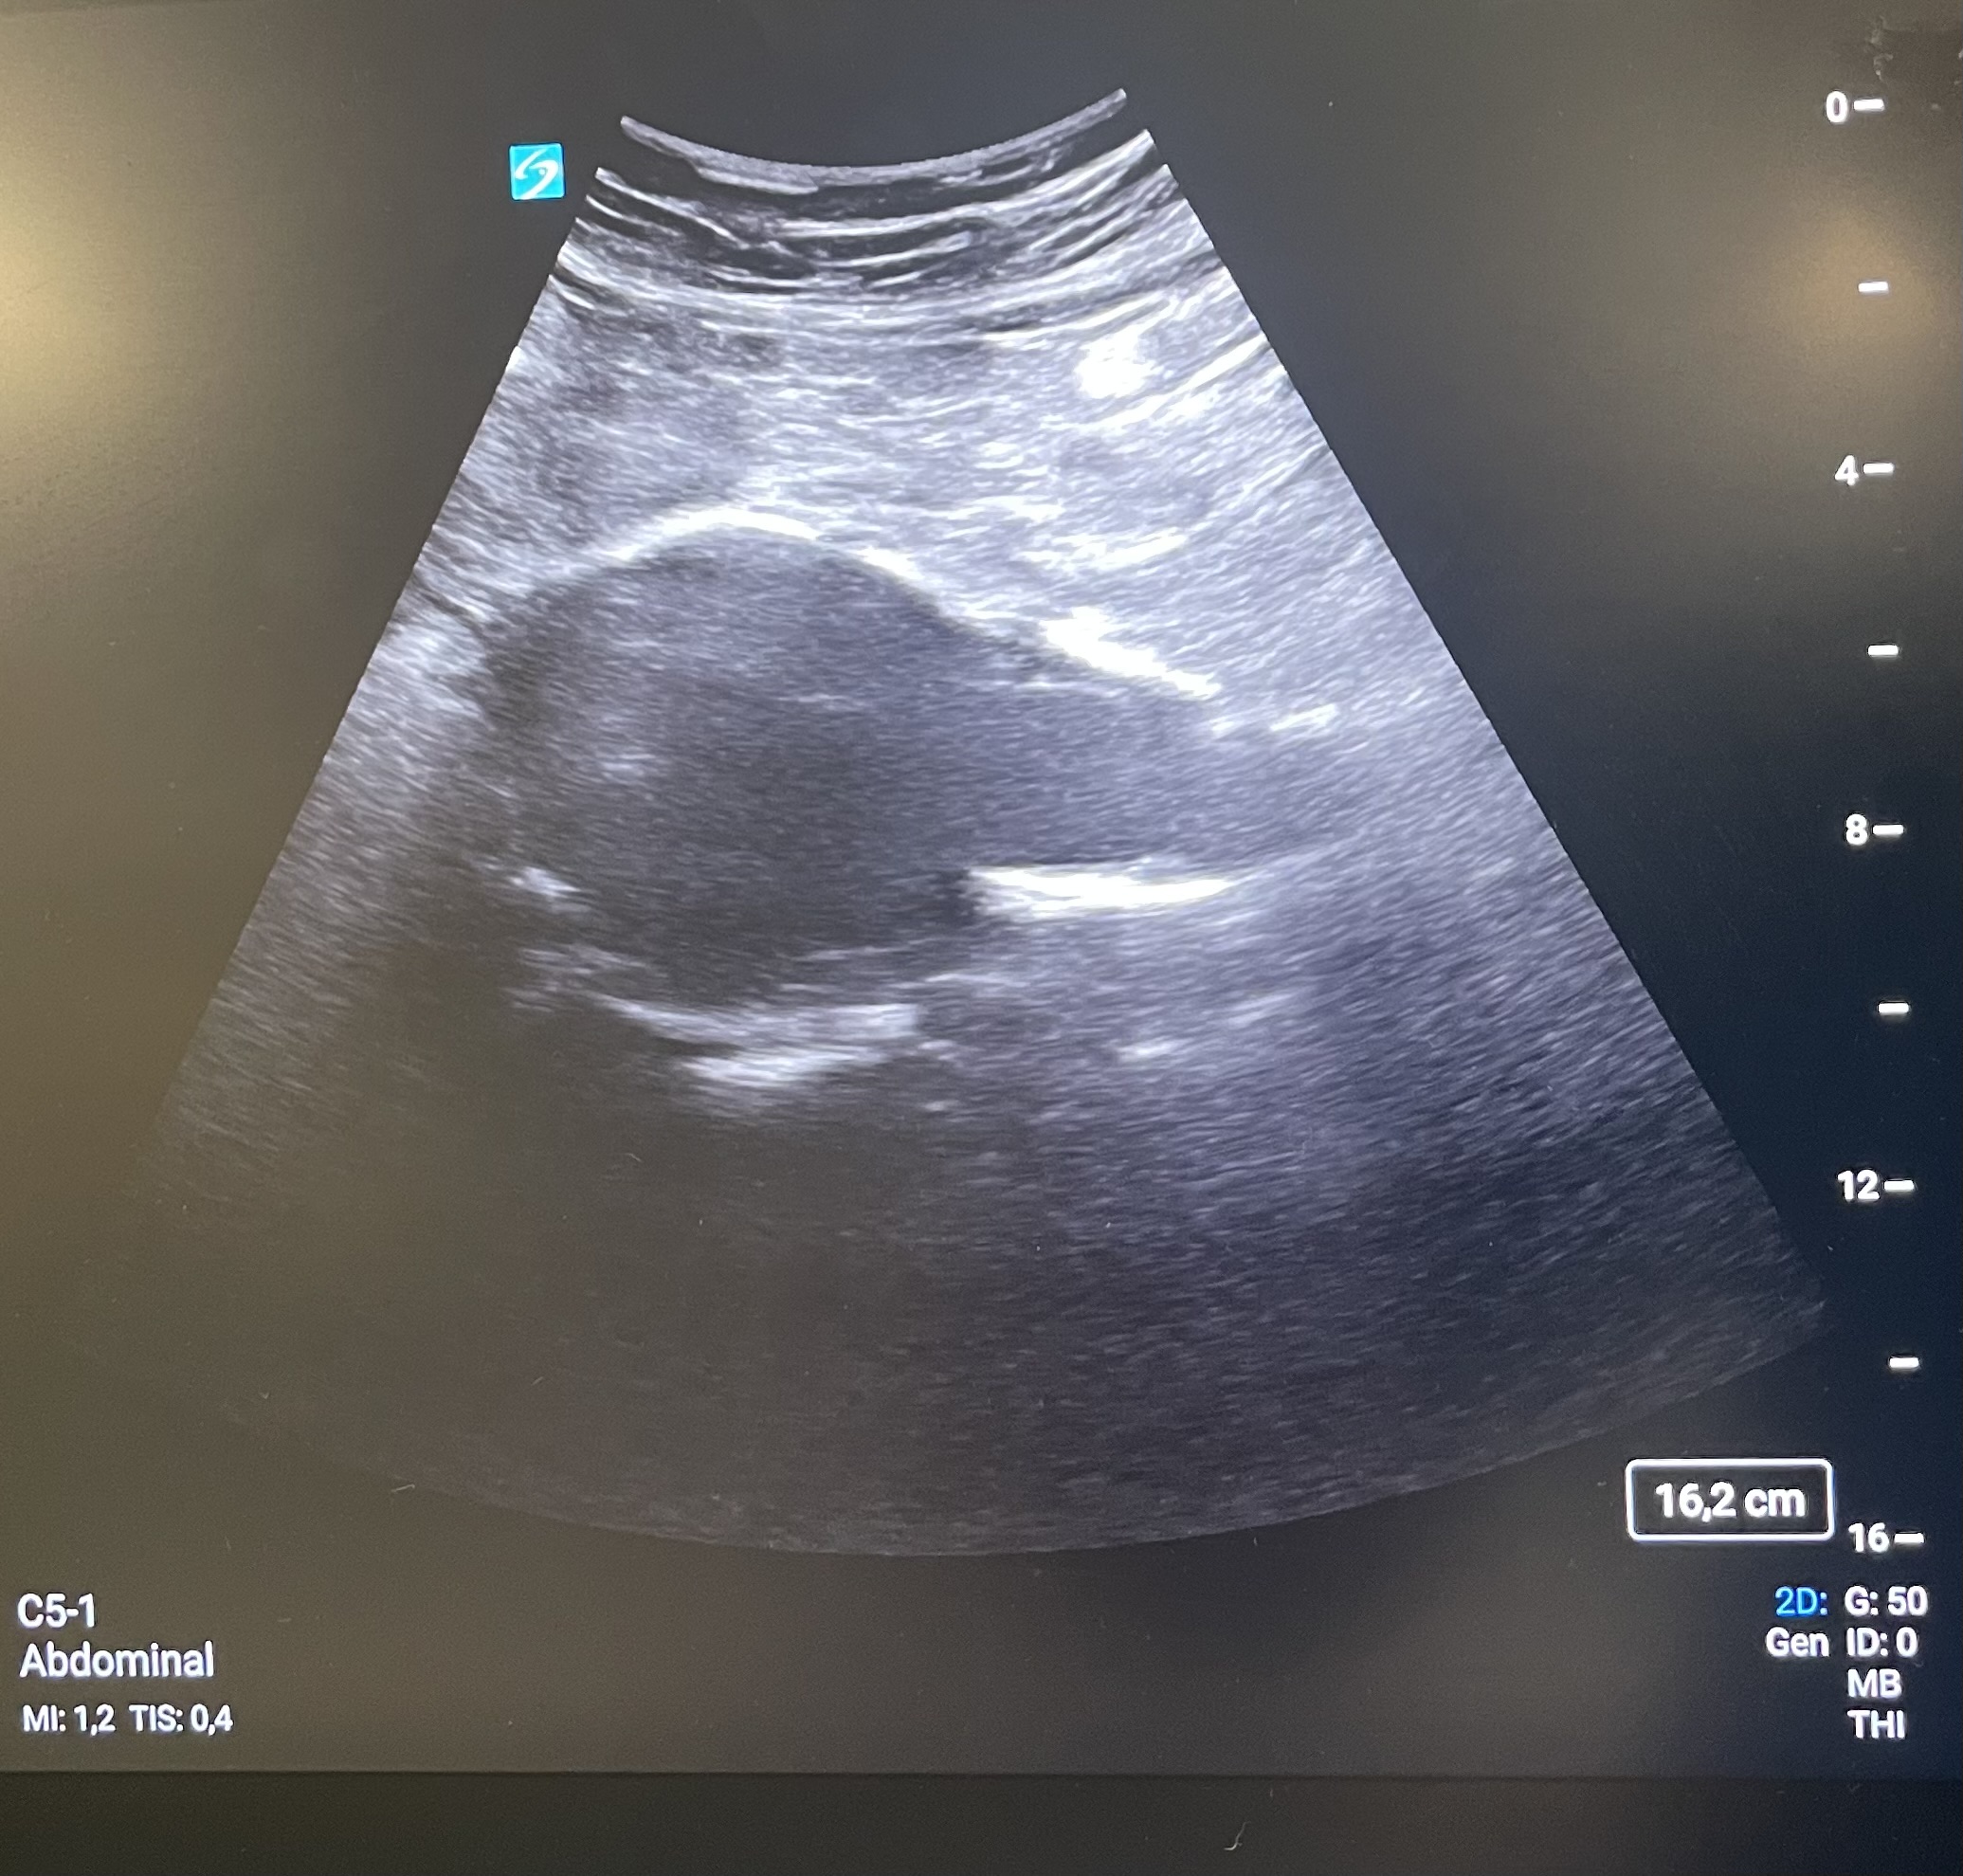

Se mantiene en la sala de reanimación de Urgencias, estable, pero con tendencia a la hipotensión y glasgow 15, para valoración por UMI y Cardiología. Tomo la iniciativa para realizar ecografía clínica para valoración de ventana cardiaca, pulmonar y grandes vasos como despistaje de “5H y 5T”.

Al valorar grandes vasos encuentro una imagen compatible con aneurisma de aorta abdominal (AAA) de 6,3 cm de diámetro con trombosis del 50% de su luz, no diagnosticado previamente. Se confirma el hallazgo en mediante TC, sin presencia de patología aórtica aguda.